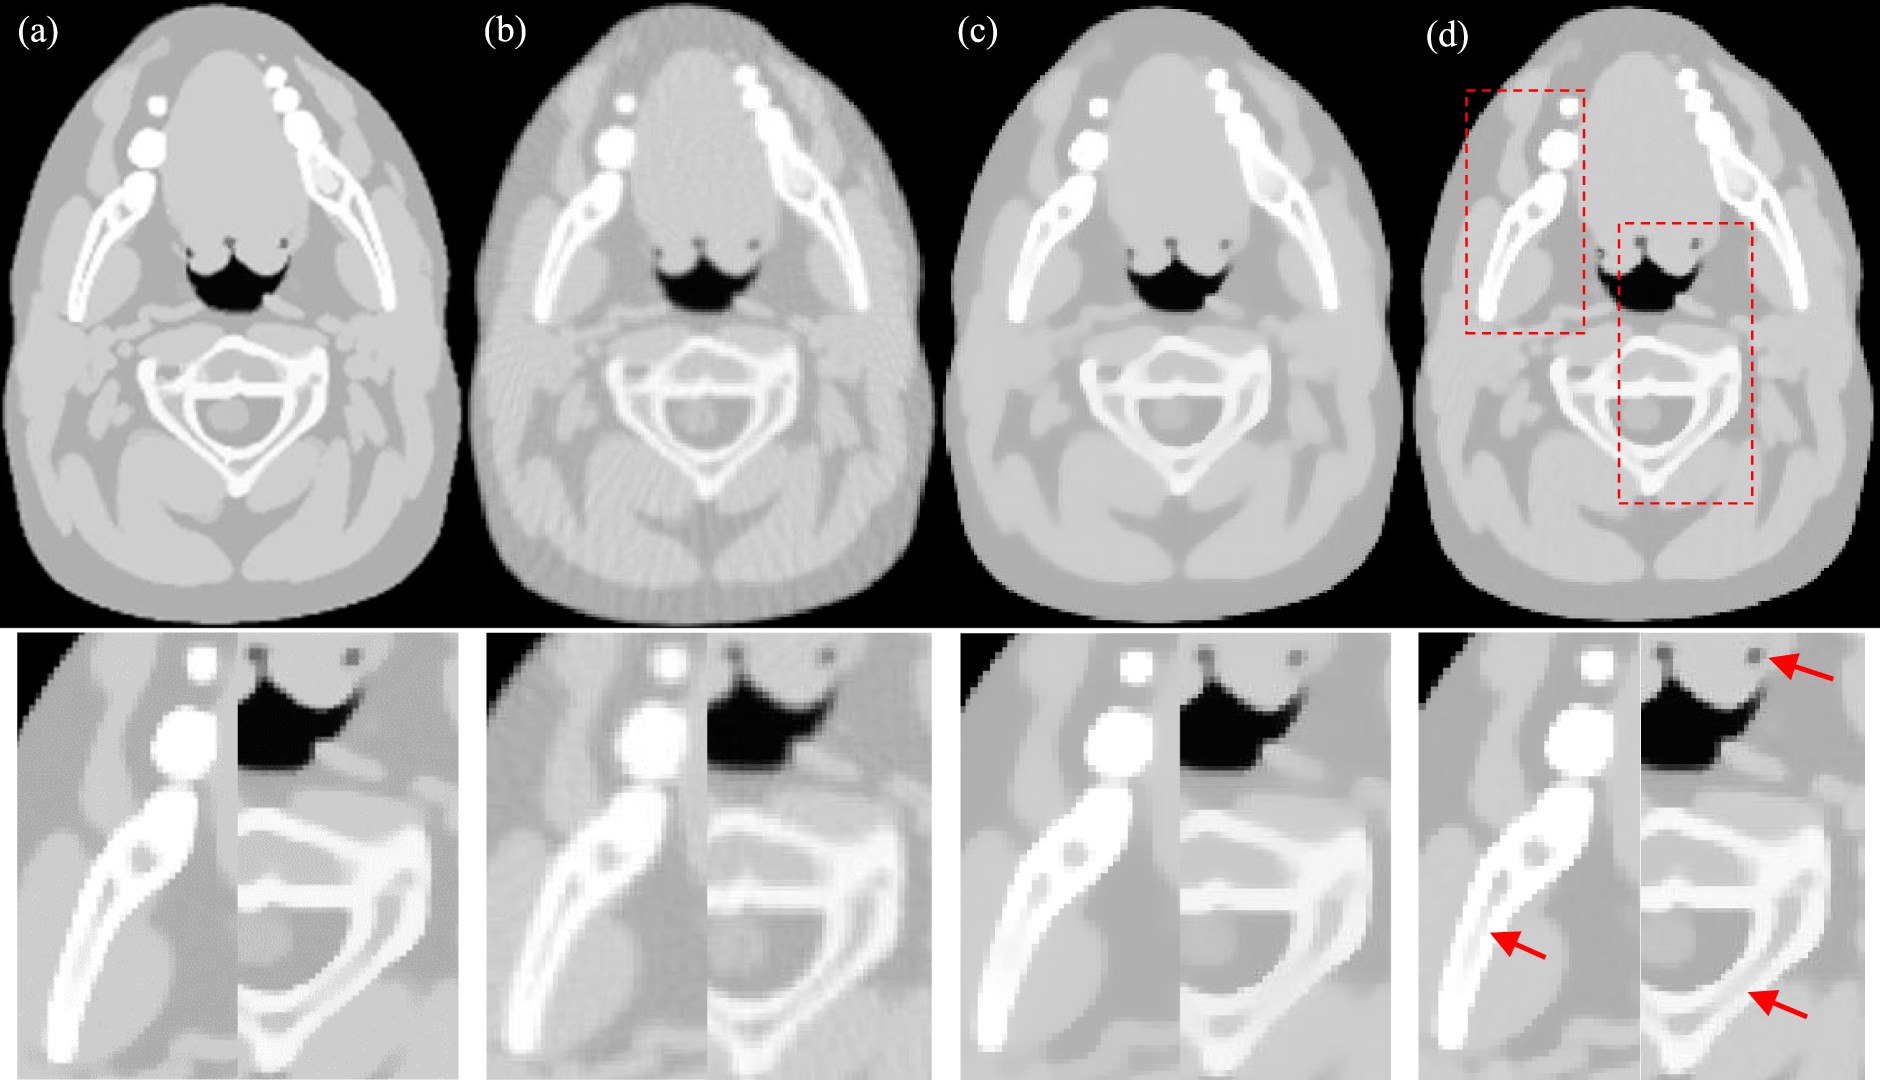

Figure 3

Reconstructed image of the head model from 120 views using different methods. The images in the second row are partially enlarged views of the first row. (a) Reference (b) FBP (c) PWLS-TV (d) PWLS-TV-FR.